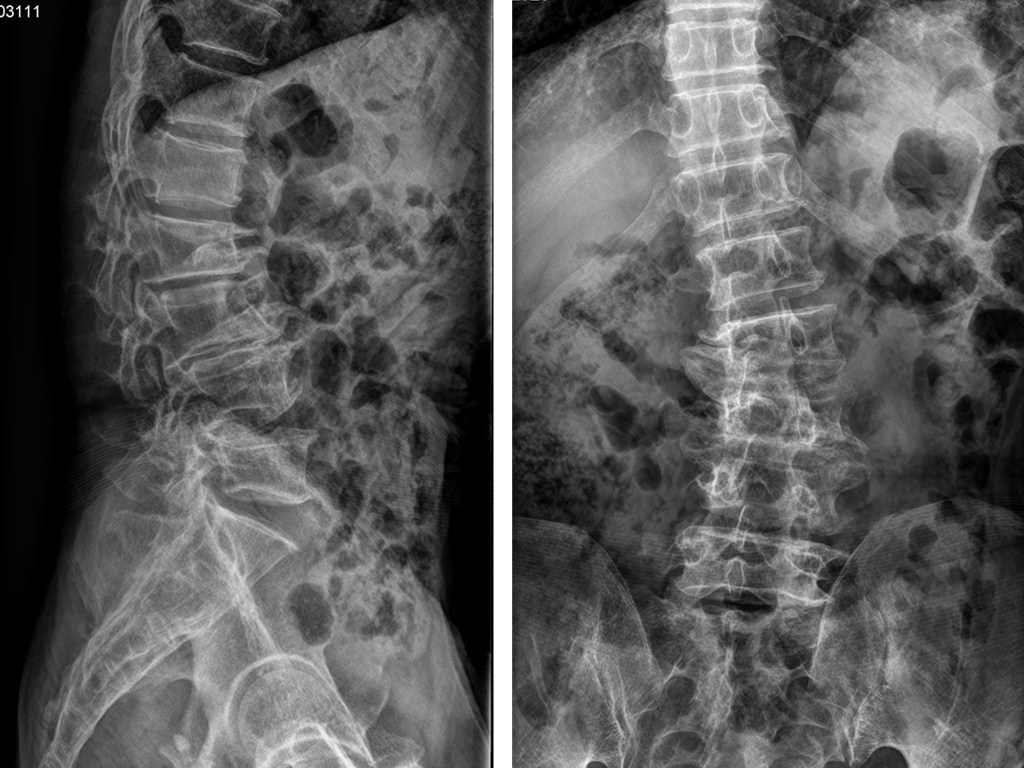

位70岁邓姓患者,因腰部及双下肢疼痛麻木严重影响正常生活而入院。我院骨伤二科团队在洪文格主任的带下结合相关检查及临床表现,诊断为退行性脊柱侧凸。

考虑到其曾就治于多家医院,经相关药物治疗、康复训练等非手术治疗效果没有缓解,我院吴成龙医生耐心的把疾病的特殊性、复杂性与患者及家属沟通,综合多方面考虑,为其施行腰椎减压内固定矫正融合手术,并精心准备手术方案。经过精心术前准备,在医护人员的通力配合下,由洪文格主任医师主持实施,手术过程十分顺利。